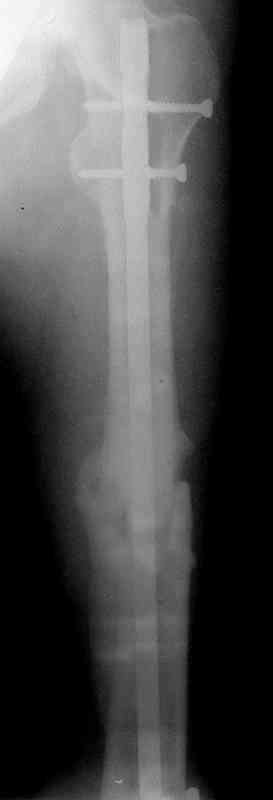

по его наружной поверхности послеоперационный рубец - рана зажила первичным натяжением. При измерении длины бедер обнаружено укорочение левого бедра на 4,5 см. На рентгенограммах этого бедра: ось конечности правильная, отмечается захождение основных костных фрагментов по длине, проксимальный конец штифта выступает слишком медиально и высоко относительно большого вертела, периостальная мозоль незначительна.22.12 - через 6 месяцев после операции, произведенной в ЦРБ, нами по поводу замедленно консолидирующего перелома левой бедренной кости с ее абсолютным укорочением под наркозом произведена операция: удаление штифта, закрытый блокирующий интрамедуллярный остеосинтез перелома левого бедра штифтом без рассверливания (UFN) длиной 40 см, диаметром 10 мм с блокированием только проксимальных отверстий (динамический остеосинтез). Наложен аппарат Илизарова на 4 полукольцах с целью удлинения укороченного бедра. Послеоперационное течение без особенностей. Ежедневно осуществляли дистракцию отломков на 1 мм. Через 3 недели после операции больной выпи-сан на амбулаторное лечение с продолжением дистракции отломков. В течение 1,5

месяцев дистракции укорочение левого бедра удалось полностью устранить. 22.02.00, т.е. через 2 месяца после повторного остеосинтеза, больному произведено дистальное блокирование штифта двумя винтами и демонтирован аппарат Илизарова. В течение 2 недель после операции больной ходил с помощью костылей, потом 2 недели с тростью. Опороспособность и функция оперированной конечности полностью восстановились через 4 недели после операции.

Фиксаторы удалены через 12 месяцев после операции, выполненной по поводу замедленной консолидации перелома бедра с его укорочением.

Спасибо! Истинно мастерская работа. Представляю как счастлив пациент исходом этой истории.

На финальных снимках видно - сращение прям таки железное. Если Вы не устали отвечать, осмелюсь задать еще вопрос - что-то принимал пациент в целях ускорения сроста (кальций, режим питания). Интересны также вопросы восстановления функций конечности - в какой период были рекомендованы группы упражнений для восстановления основных групп мышц?